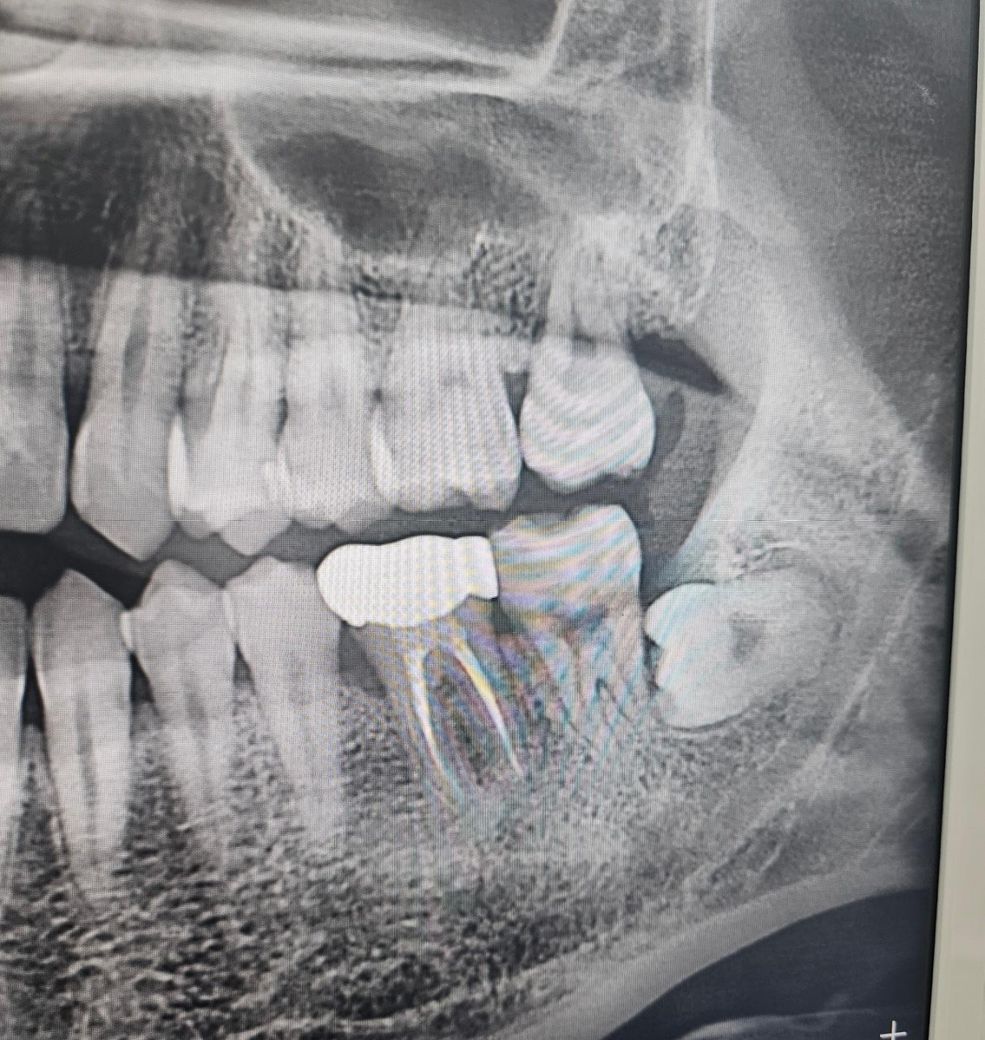

인접면충치 전문가분들의 의견이 궁금합니다

현재 오른쪽 아랫니 (아마46번?) 빼고는 시리거나 아픈건 없습니다

• 3번 째 사진